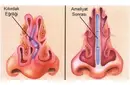

Fibröz kıkırdak, genellikle fibroblastlar tarafından üretilen kolajen tip I lifleri içerir. Bu lifler, kıkırdağın dayanıklılığını ve esnekliğini artıran bir ağ oluşturur. Fibröz Kıkırdak Türleri Fibröz kıkırdak, genel olarak iki ana türde bulunur:

Fibröz kıkırdak, genellikle eklemlerde, disklerde ve tendonlarda bulunur. Özellikle omurgada intervertebral disklerde ve bazı eklemlerde önemli bir rol oynar. Fibröz Kıkırdağın Fonksiyonları Fibröz kıkırdak, vücutta birçok önemli işlevi yerine getirir:

Fibröz kıkırdak, travma veya aşınma sonucu zarar görebilir. Bu tür durumlarda, kıkırdak onarım süreçleri yavaş ilerleyebilir ve genellikle cerrahi müdahale gerektirebilir. Fibröz Kıkırdak Hastalıkları Fibröz kıkırdak ile ilişkili bazı hastalıklar ve durumlar şunlardır: